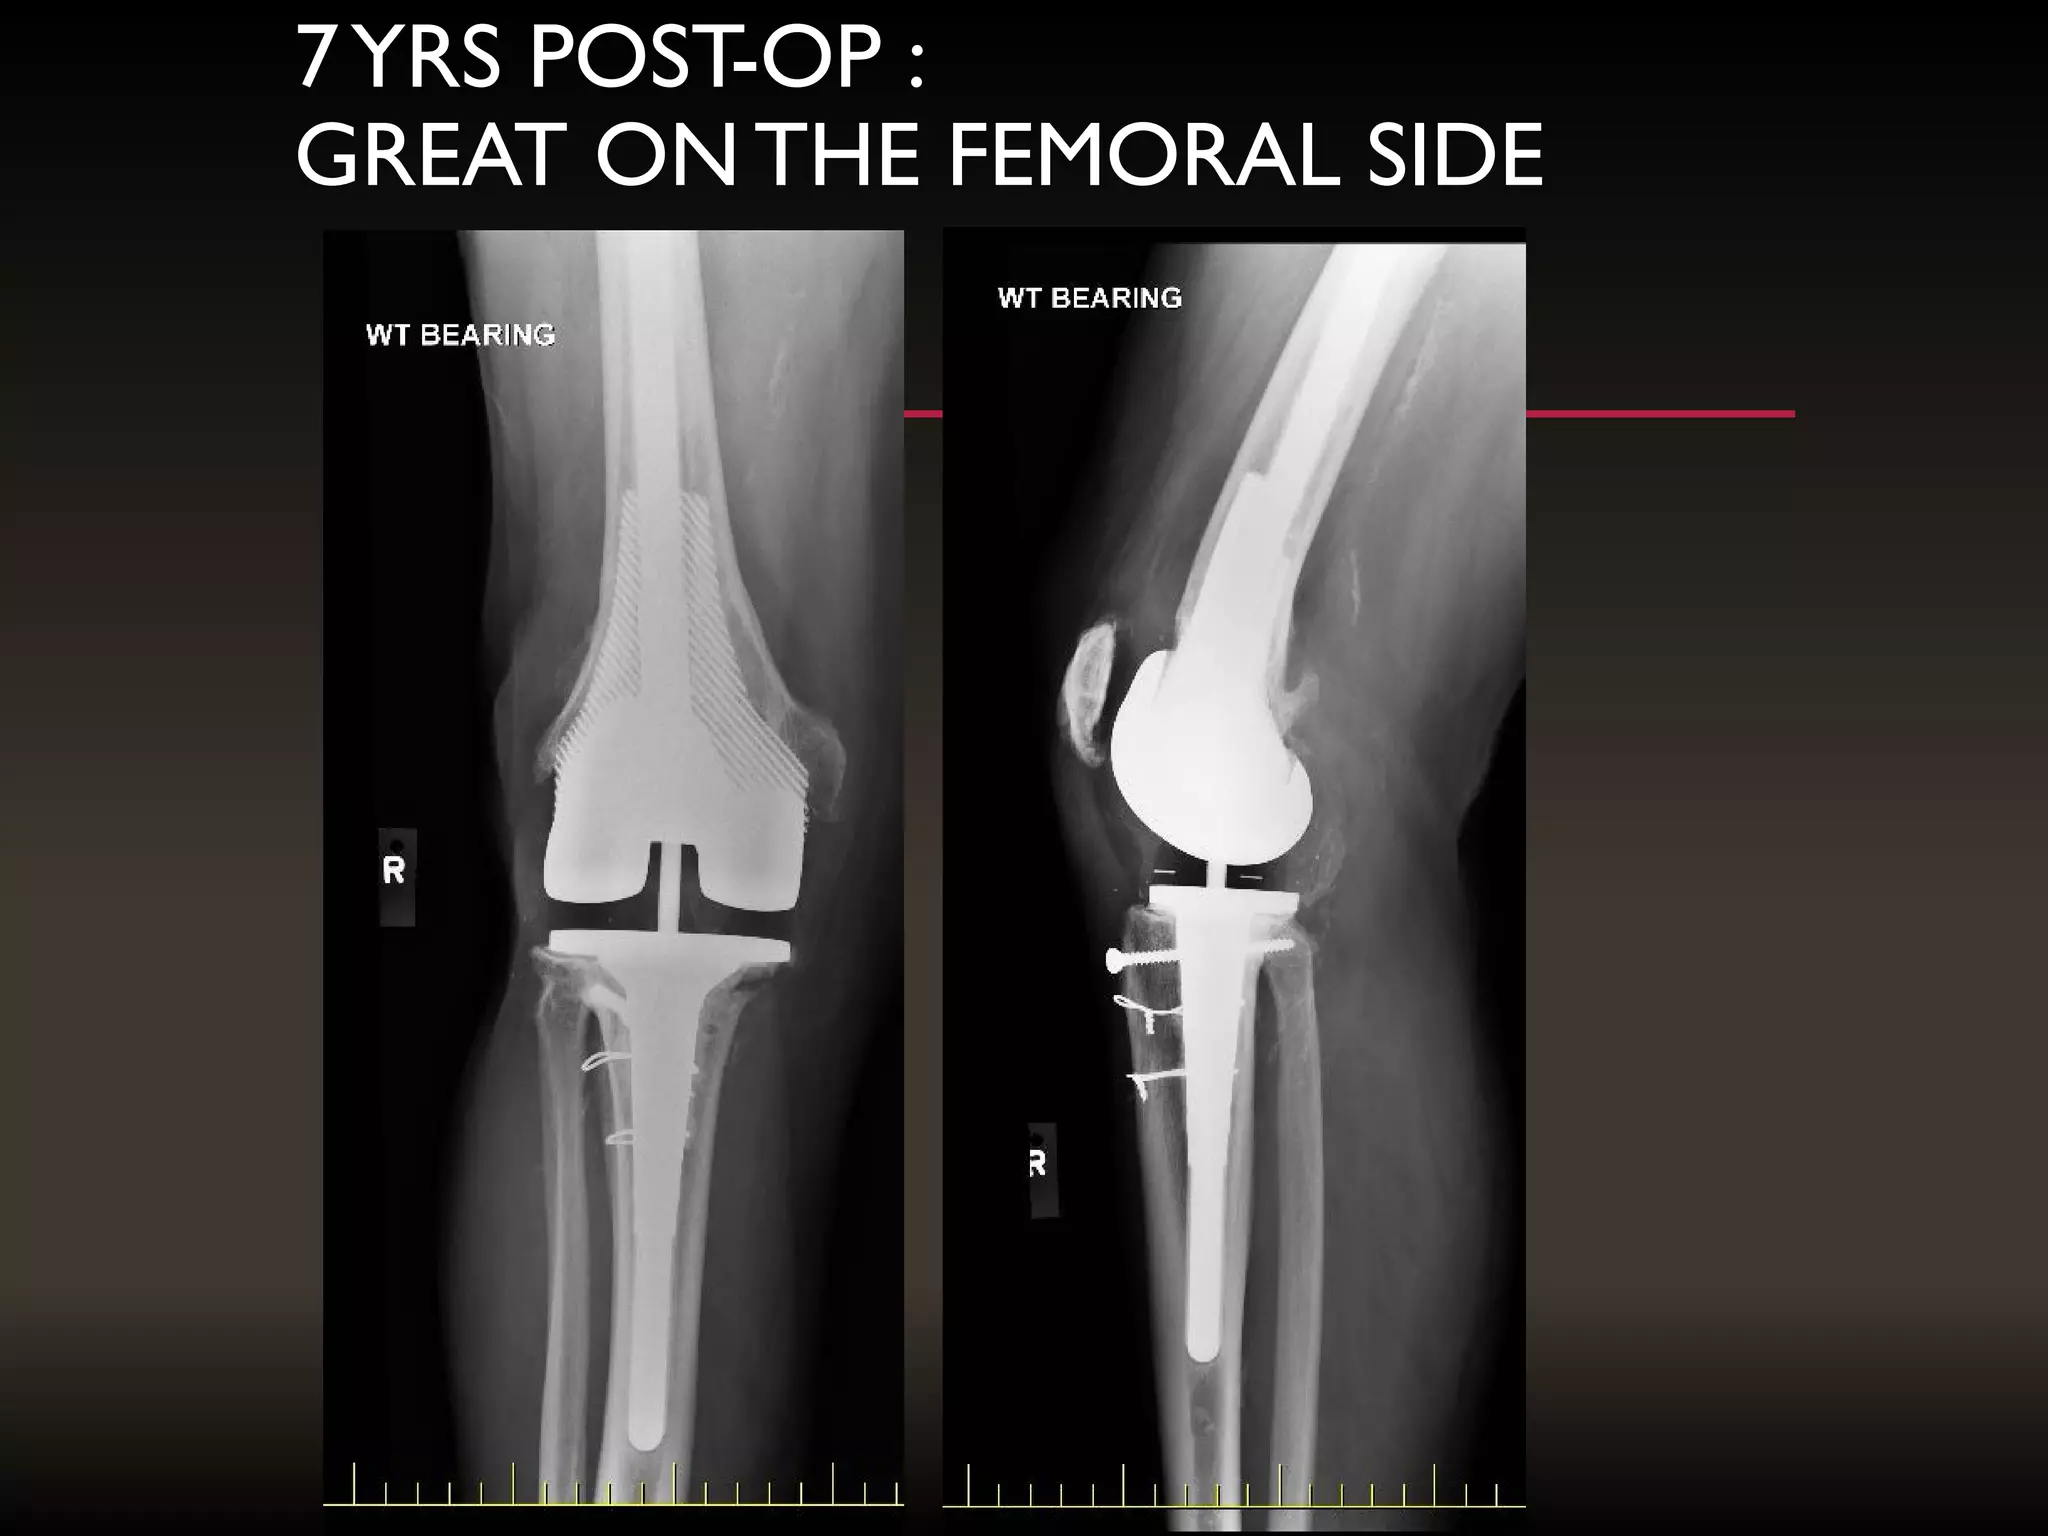

7YRS POST-OP :

GREAT ONTHE FEMORAL SIDE

7YRS POST-OP : GREATONTHE FEMORAL SIDE

INTERFACES

ARE

EXCELLENT

POORER

ON TIBIAL SIDE